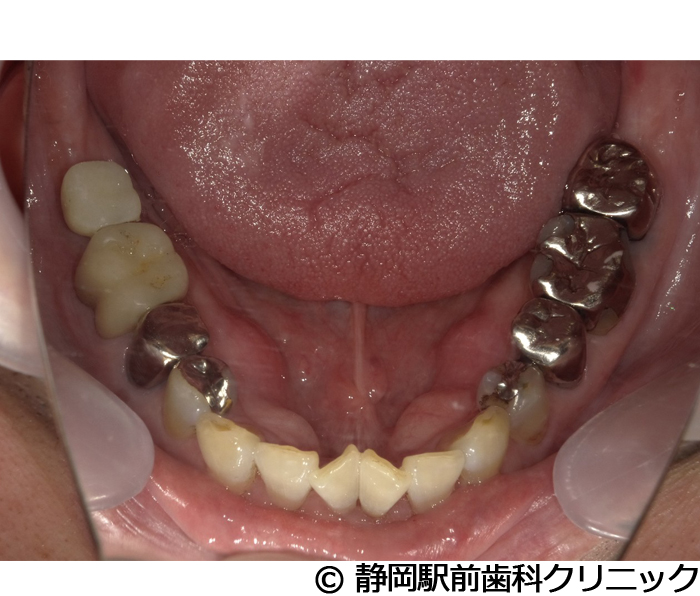

【症例5】全顎的インプラントとセラミックによる審美補綴

- 治療前

- 治療後

- 治療名

- 全顎的インプラントとセラミックによる審美補綴

- 費用

- 1,800,000円(税込)

- 期間

- 1年6ヵ月

治療内容

患者様の症状

-

全体的に歯がないため、噛めない。インプラント治療希望。

治療方法

全体的に残根は抜歯を行い、術前にCTを撮影し緻密に治療計画を立てた。インプラント埋入はブロックごとに行い、噛み合わせの調整を重ねた後、人工歯を被せて咬合と審美の回復を行いました。

治療結果

しっかり奥歯で食べ物を噛み切ることができるようになり、何でも食べることができるようになったと喜んでいただくことができました。口元を気にせずに笑うこともできるようになり、見た目もキレイになったとご満足いただけました。

※治療結果は個人差があります。

治療を行う上での注意点(リスク・副作用)

術後は、出血、腫れ、痛みなどが出る可能性があります。